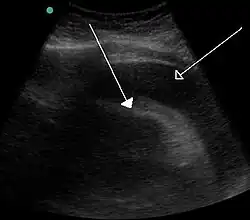

![]() Tamponada serca spowodowana krwistym wysiękiem do worka osierdziowego w przebiegu choroby nowotworowej, obraz USG | |